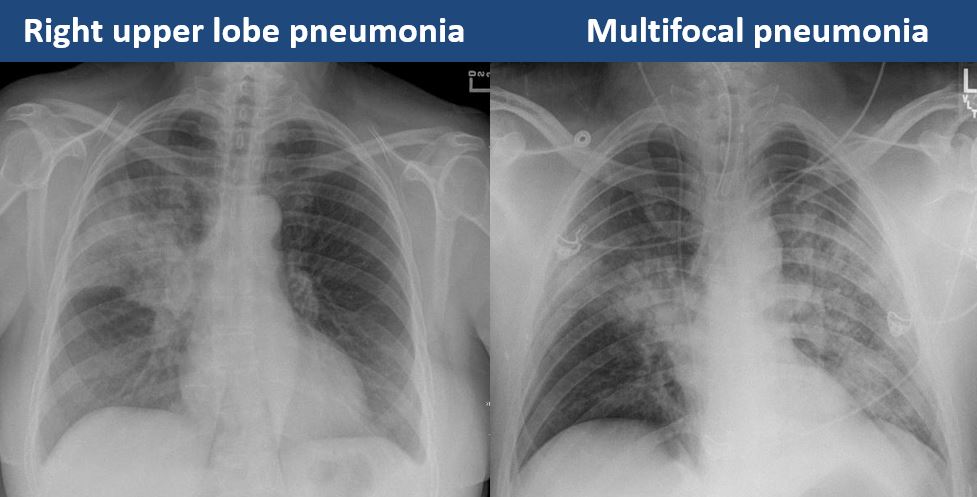

There is focal or diffuse interstitial disease. |

yes | NA |

There is focal or lobar atelectasis or total collapse of the lung. |